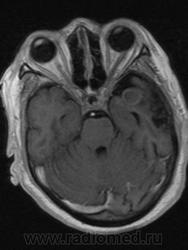

это частично тромбированная аневризма левой СМА, и постинсультные дела..